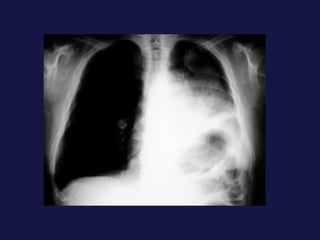

Carcinoma de células pequeñas   (18-25%). Peor pronóstico en  cuanto a supervivencia, responde bien a la quimioterapia. Variedad que mas da smes paraneoplasicos. 90% en bronquios centrales. SME de la vena cava superior. Localización central.

Tumor central. 60-75% próximos a los hilios. Epidermoides y células pequeñas. Agrandamiento asimétrico del hilio o masa de bordes espiculados. Atelectasia lobular, segmentaria o de todo el pulmón. Sobreinfección del parénquima distal y neumonía postobstructiva, a menudo abscesificada.

Carcinoma de célulaspequeñas (18-25%). Peor pronóstico en cuanto a supervivencia, responde bien a la quimioterapia. Variedad que mas da smes paraneoplasicos. 90% en bronquios centrales. SME de la vena cava superior. Localización central.

Tumor central. 60-75%próximos a los hilios. Epidermoides y células pequeñas. Agrandamiento asimétrico del hilio o masa de bordes espiculados. Atelectasia lobular, segmentaria o de todo el pulmón. Sobreinfección del parénquima distal y neumonía postobstructiva, a menudo abscesificada.